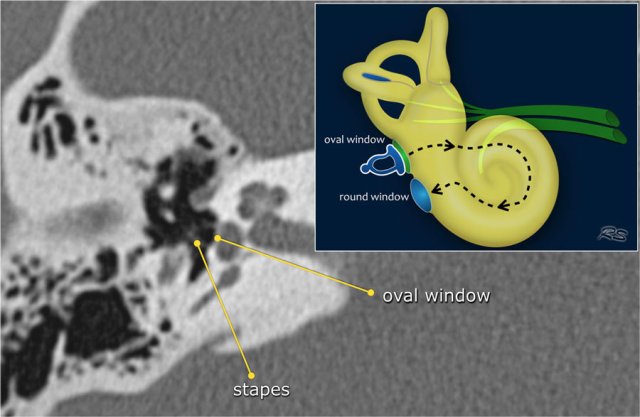

Oval and round window

The base of the stapes rocks in and out against the membrane in the oval window.

The vibrations are transmitted from the oval window via the endolymph to the hair cells of the organ of Corti in the cochlea.

The round window dissipates the pressure generated by the fluid vibrations within the cochlea and thus serves as a release valve.